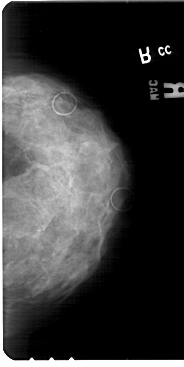

A_1852_1.LEFT_CC

LEFT_CC LINES 5491 PIXELS_PER_LINE 2911 BITS_PER_PIXEL 12 RESOLUTION 43.5 OVERLAY

FILE: A_1852_1.LEFT_CC.OVERLAY

TOTAL_ABNORMALITIES 1

ABNORMALITY 1

LESION_TYPE CALCIFICATION TYPE PUNCTATE DISTRIBUTION CLUSTERED

ASSESSMENT 4

SUBTLETY 2

PATHOLOGY MALIGNANT

TOTAL_OUTLINES 1

BOUNDARY